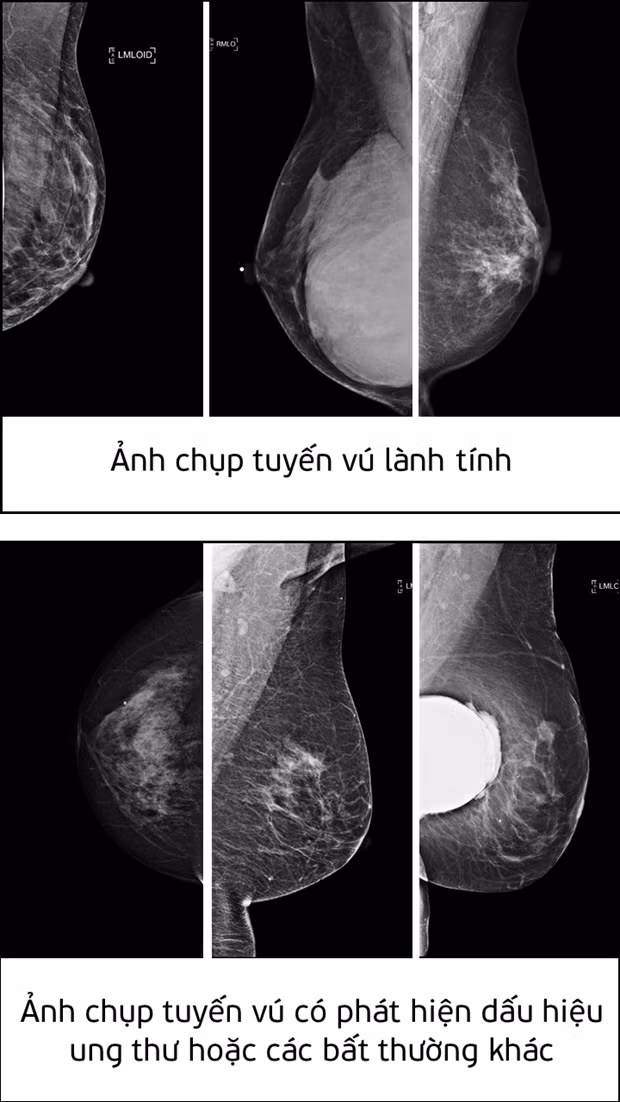

| Ảnh chụp tuyến vú lành tính và ảnh chụp tuyến vú có phát hiện dấu hiệu ung thư hoặc các bất thường khác. |

Giải pháp AI do Nguyễn Hồng Đăng phát triển có thể tự động nhận diện các dấu hiệu bệnh ung thư tuyến vú từ một vùng rất nhỏ trong nhũ ảnh. Giải pháp này có thể tích hợp vào hệ thống hỗ trợ phân tích (Computer-aided diagnosis - CADx systems) nhằm cải thiện tính chính xác trong việc chẩn đoán và khám chữa bệnh.

Theo đánh giá của Ban giám khảo, giải pháp của Nguyễn Hồng Đăng đã giải quyết được tình trạng mất cân bằng dữ liệu trong huấn luyện mô hình AI. Trong tệp dữ liệu mà cuộc thi đưa ra, tỷ lệ mẫu ung thư ác tính được gán nhãn chỉ chiếm khoảng 2% tổng số lượng mẫu, trong khi số lượng mẫu còn lại được gán nhãn lành tính hoặc bình thường chiếm 98%. Tình trạng mất cân bằng dữ liệu này có thể khiến cho trí tuệ nhân tạo dự đoán sai.